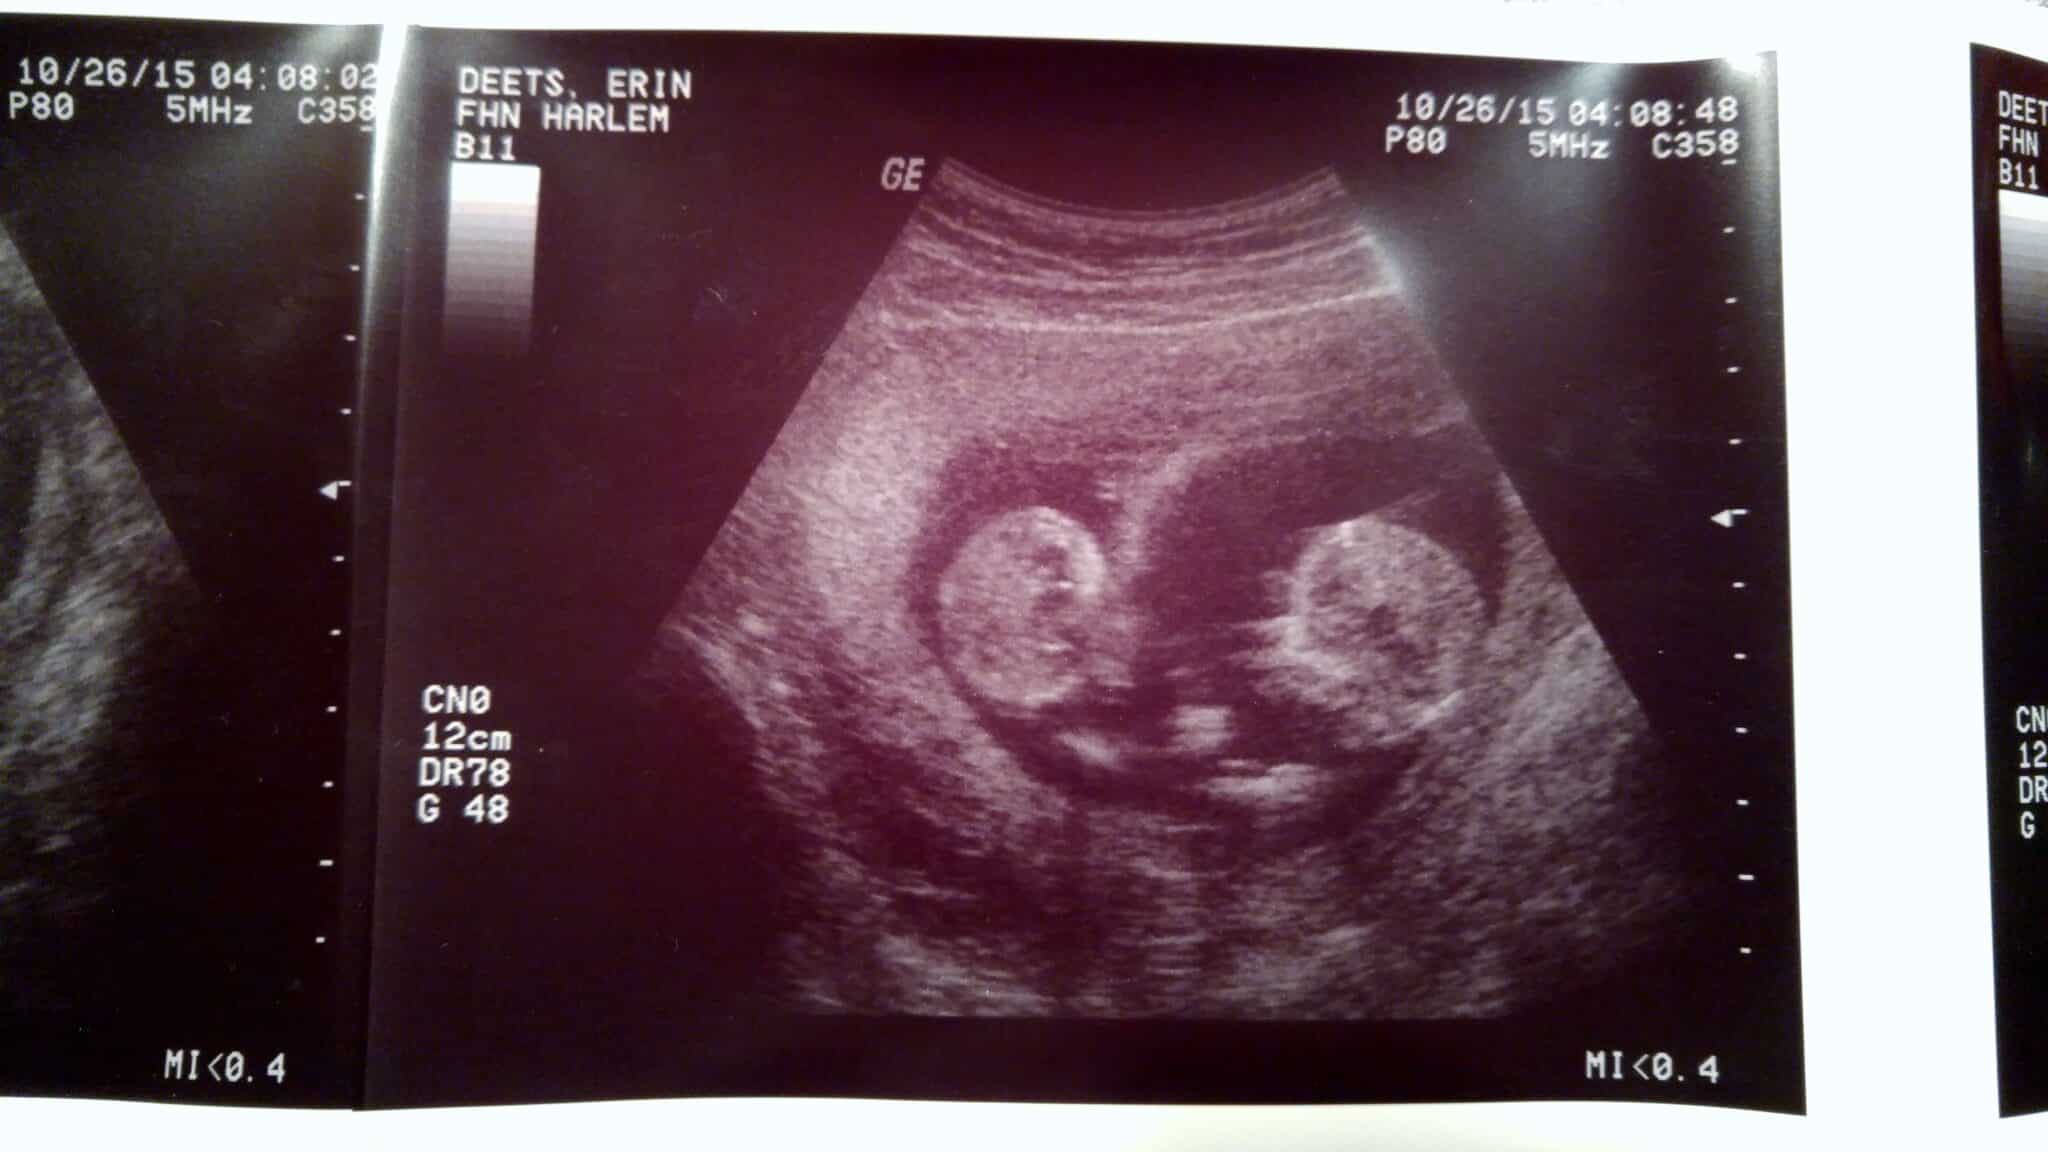

Ultrasound Photos at 12 Weeks Pregnant With Twins